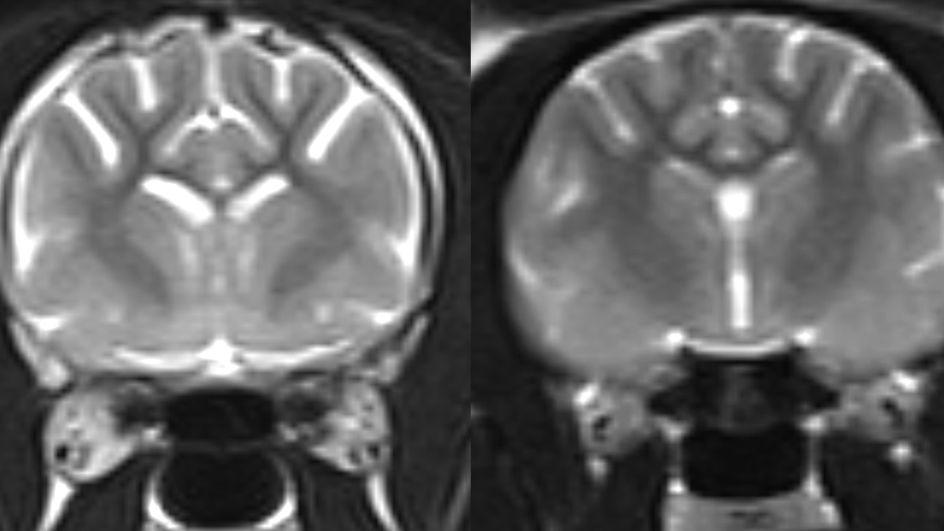

As áreas claras na imagem de ressonância magnética à esquerda mostram maior perda de tecido cerebral em um gato vivo com demência, em comparação com um cérebro felino normal, mostrado à direita Crédito: University of Edinburgh

As sinapses permitem a passagem de mensagens entre as células cerebrais, e a perda delas causa redução da memória e das habilidades de raciocínio em humanos com Alzheimer.

A equipe acredita que a descoberta em gatos pode ajudá-los a compreender melhor esse processo, oferecendo um modelo valioso para estudar a demência em pessoas.